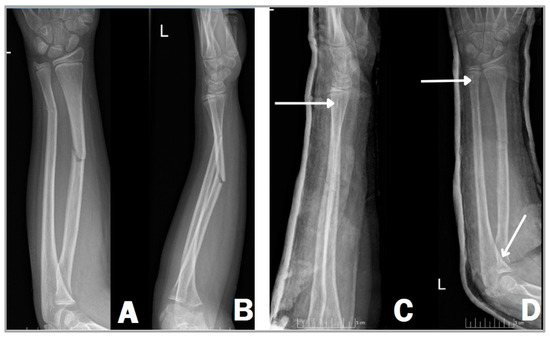

2.5. Operative Method with Resorbable Intramedullary Nail (RESIN)